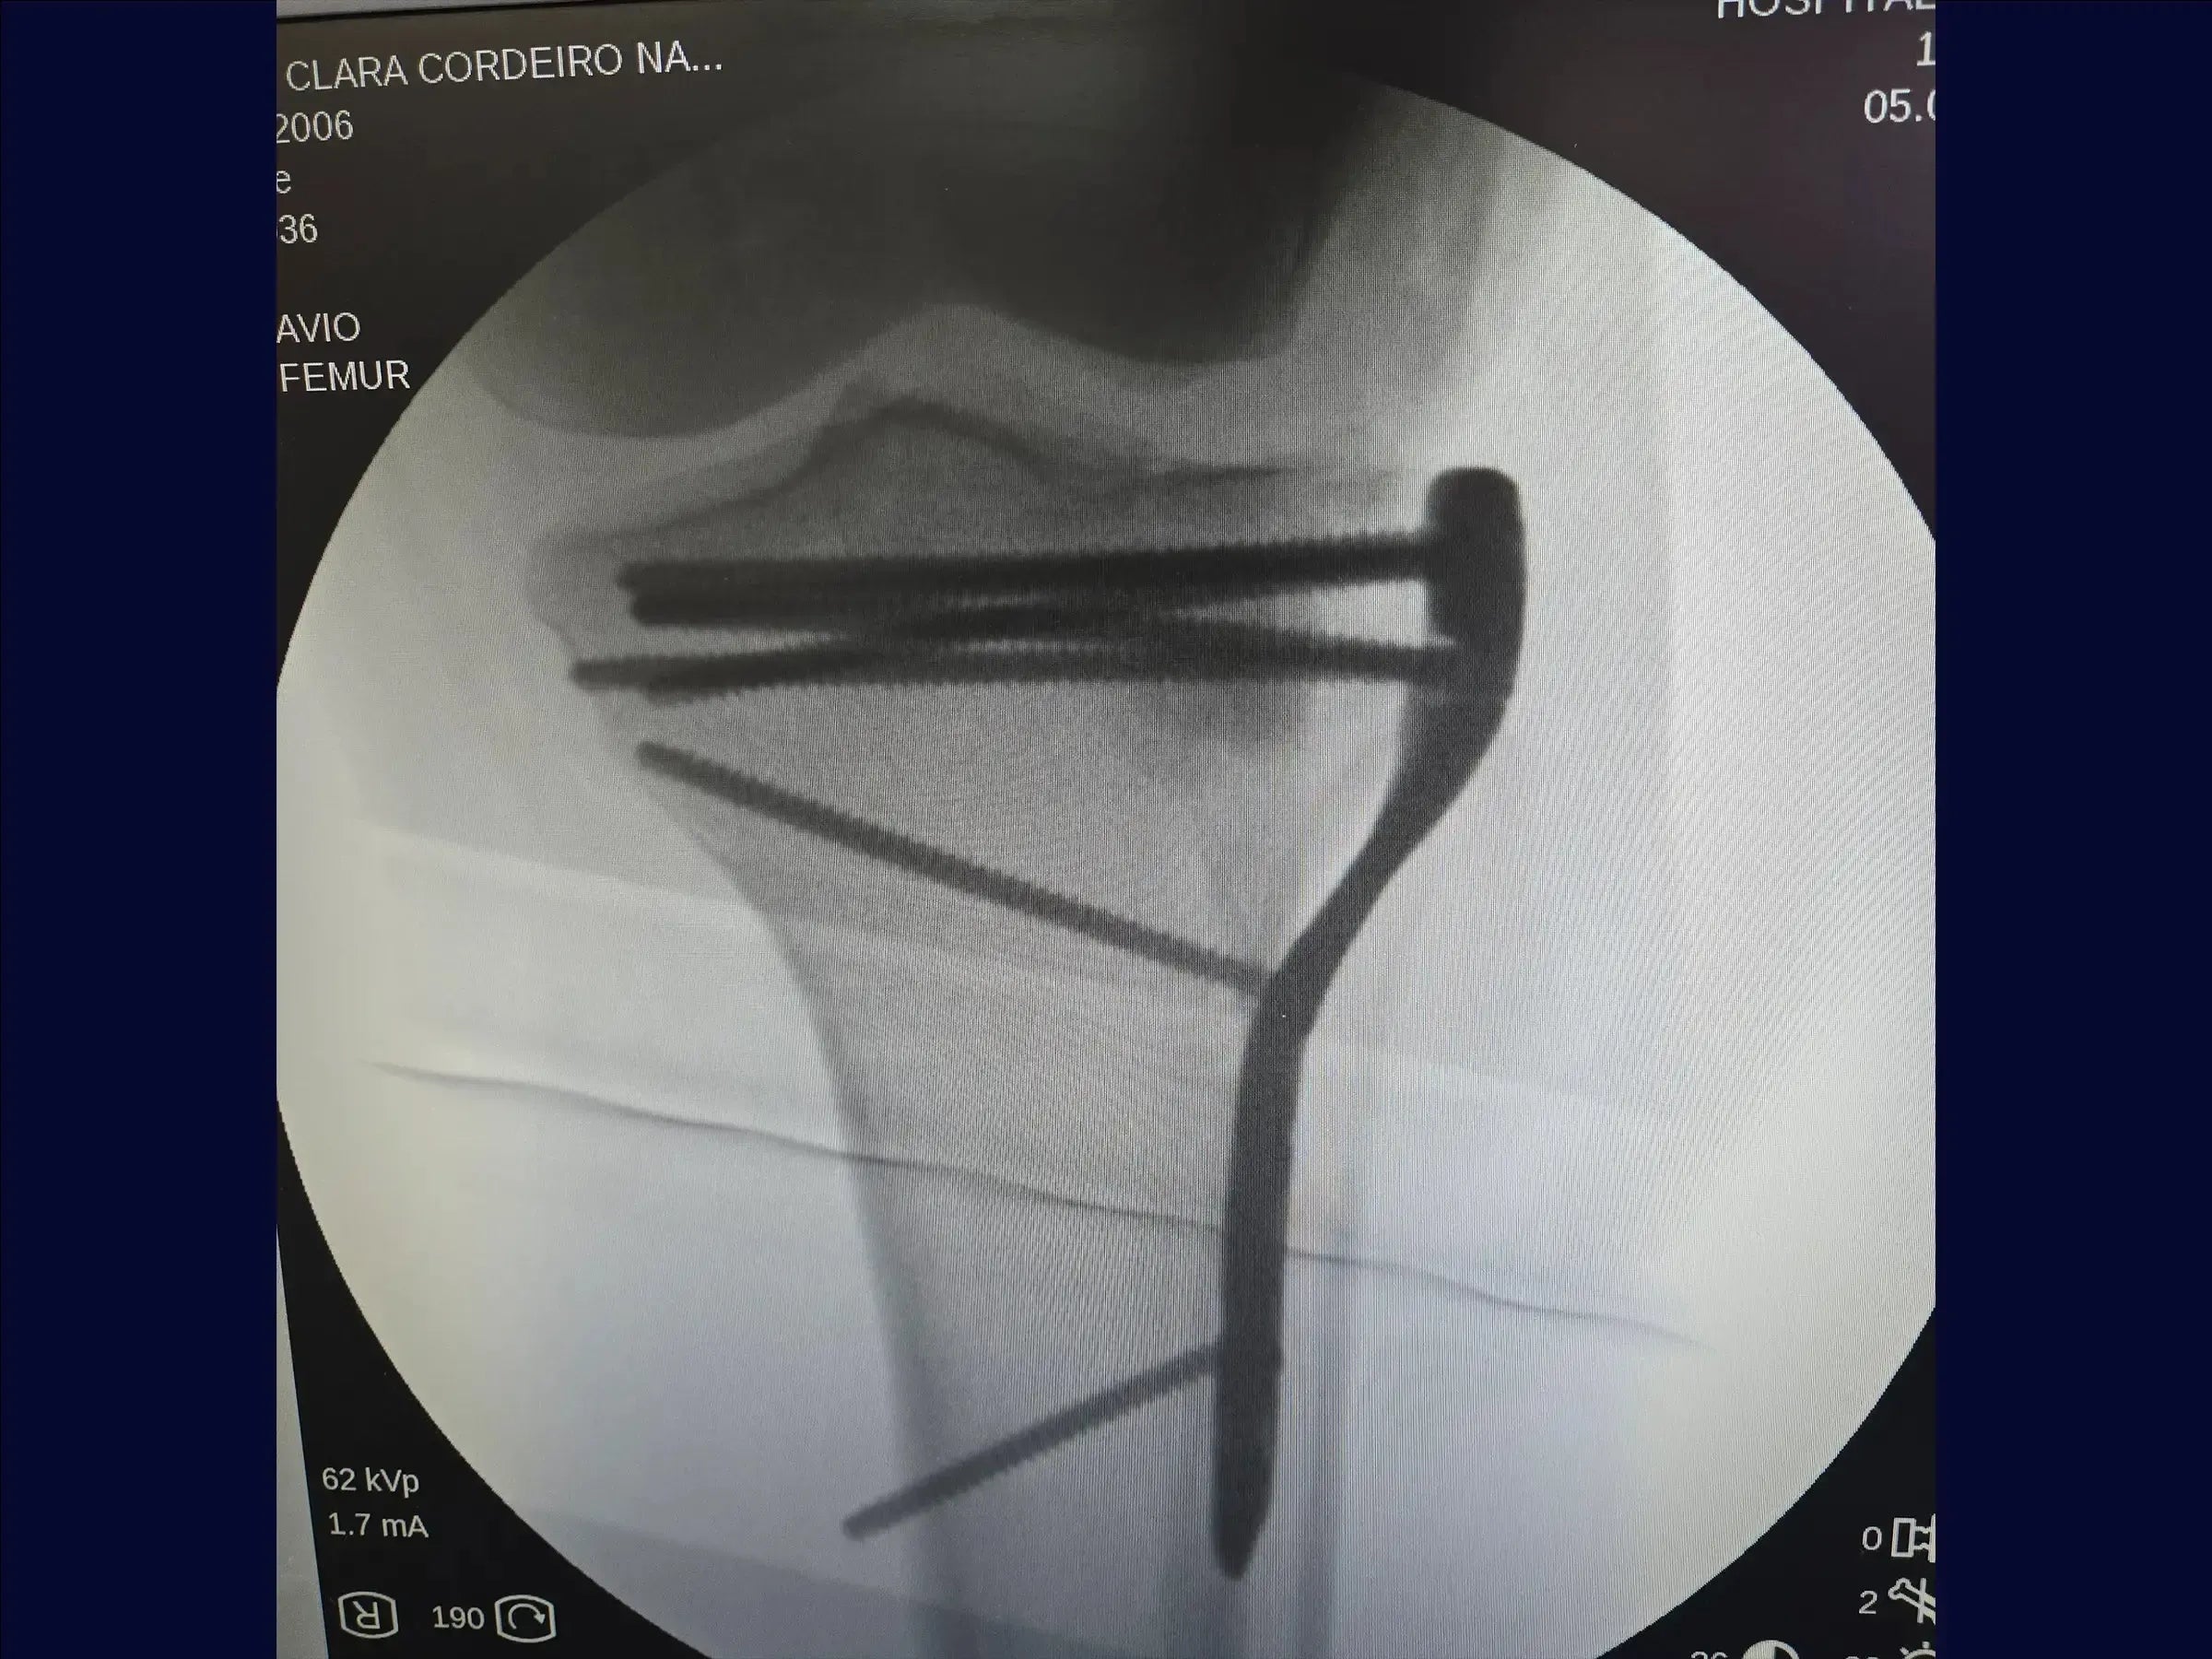

- Fijación con placa y tornillos para reducción y estabilización anatómica.

- Elevación precisa de la depresión: metodología para levantar el bloque óseo impactado de manera uniforme, con sobrecorrección discreta para la acomodación y estabilidad del injerto, utilizando control bimanual.

- Estrategia de Fijación Estable: Aplicación de la placa con tornillo en un punto estratégico para la compresión inicial, seguido de la inserción de tornillos bloqueados subcondrales , formando una red de soporte articular.